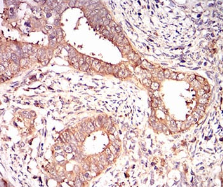

| AC2131 | EIF2A Mouse Monoclonal antibody[3A711] | 100ug | $367 | 10days |

| AC2131 | EIF2A Mouse Monoclonal antibody[3A711] | 200ug | $660.6 | 10days |